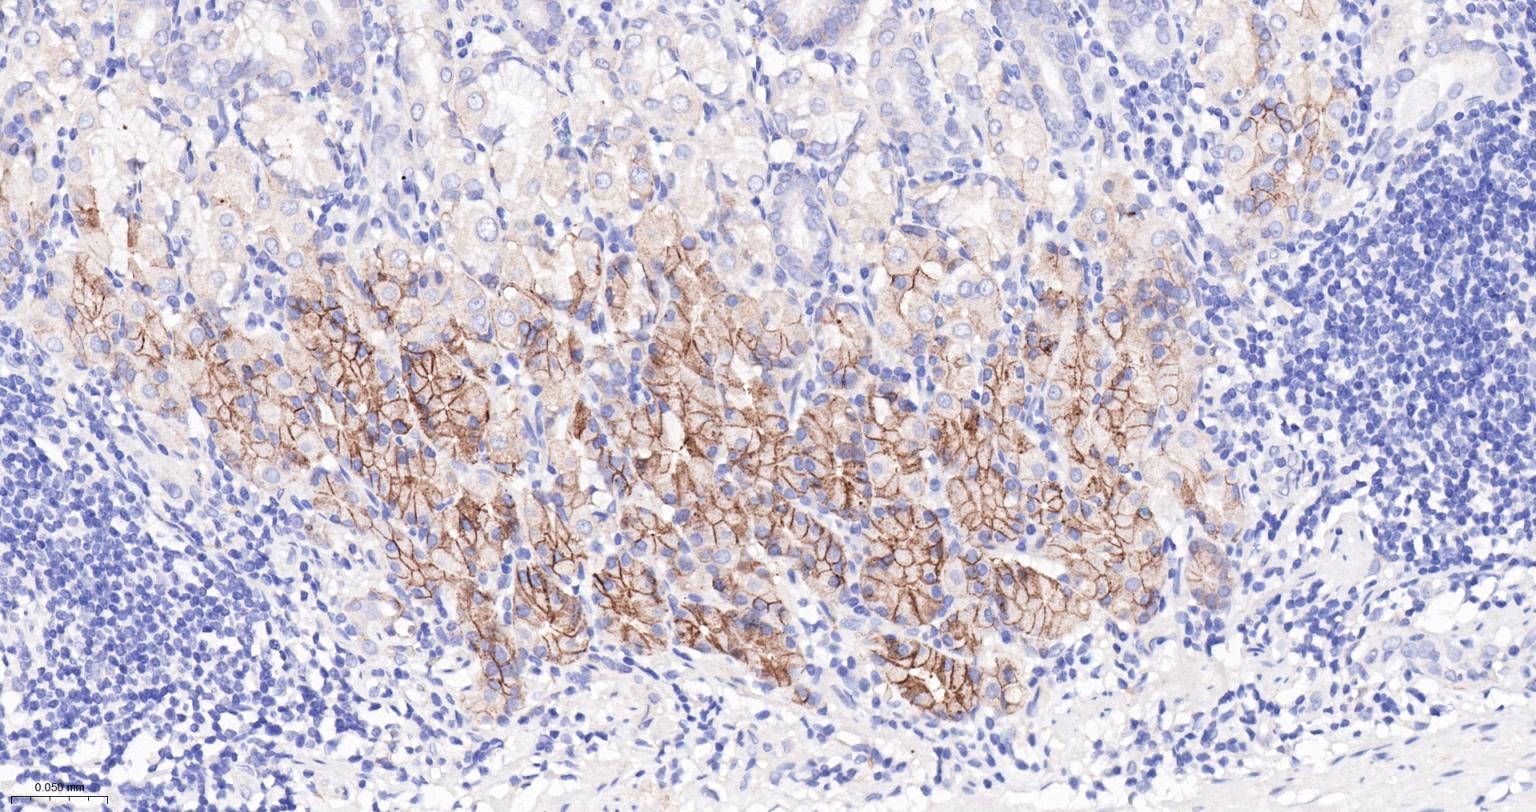

Paraformaldehyde-fixed, paraffin embedded Human Fundus; Antigen retrieval by boiling in sodium citrate buffer (pH6.0) for 15 min; Antibody incubation with CA9 Monoclonal Antibody, Unconjugated(bsm-61234R) at 1:200 overnight at 4°C, followed by conjugation to the SP Kit(Rabbit, SP-0023) and DAB (C-0010) staining.

Paraformaldehyde-fixed, paraffin embedded Human Stomach; Antigen retrieval by boiling in sodium citrate buffer (pH6.0) for 15 min; Antibody incubation with CA9 Monoclonal Antibody, Unconjugated(bsm-61234R) at 1:200 overnight at 4°C, followed by conjugation to the SP Kit(Rabbit, SP-0023) and DAB (C-0010) staining.